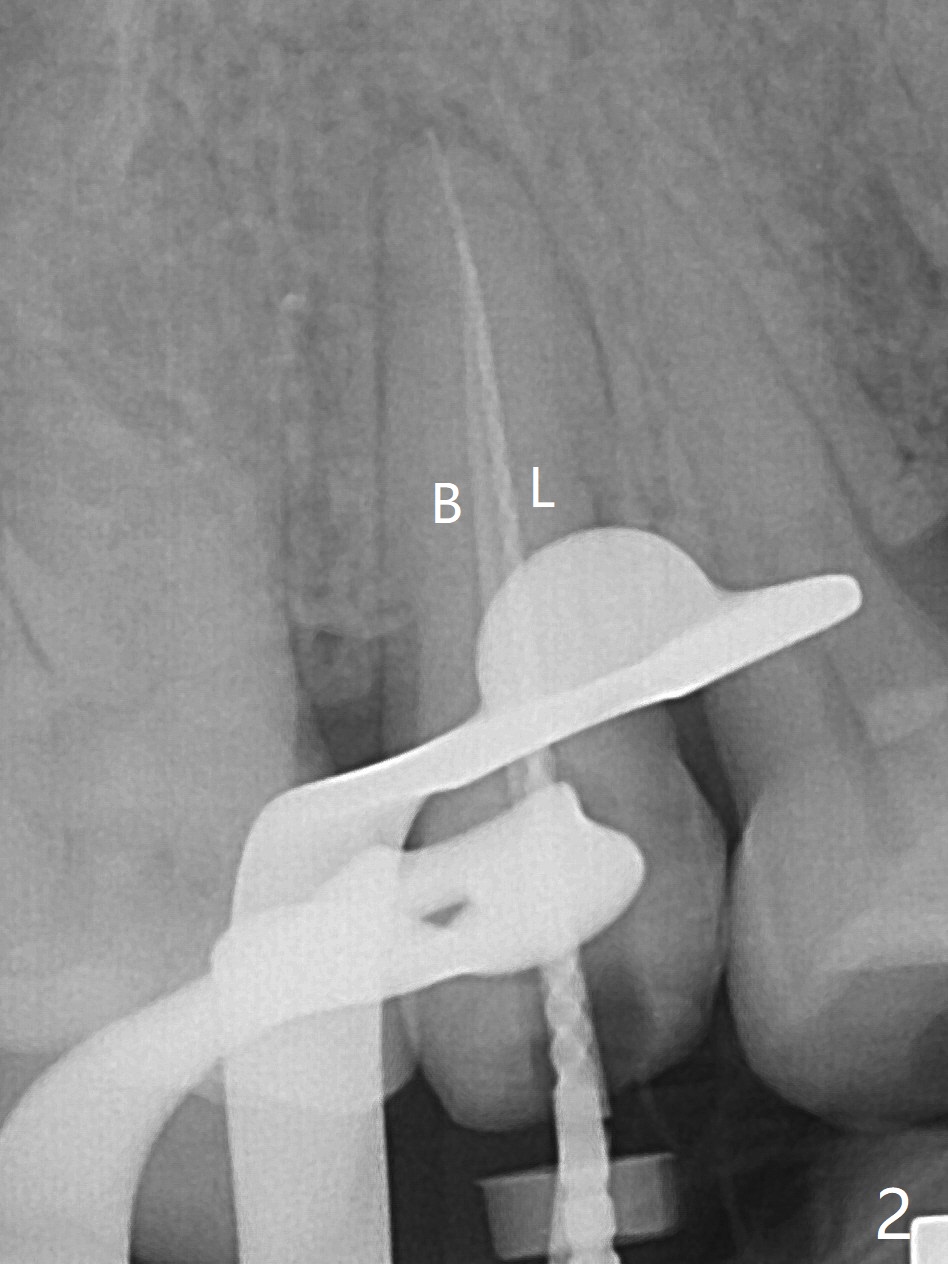

52岁女去年在外州开始4号牙根管治疗(图一),由于新冠病毒和搬家而拖延治疗,现在要求完成根管治疗(图二,三),B: 颊侧(主牙胶尖:20/.04);L: 舌侧(旋转锉:20/.04)。Shining口扫(图四(咬合面观),五(舌侧观),六(颊侧观;对合:局部托牙 (RPD)))。为了保险起见,要求实验室制作两个牙冠:取模,口扫。帮助实验室建立完善数字化系统,从而帮助临床工作。备牙边缘清晰(图八)。牙冠边缘与数字模型(图九)和牙齿吻合,天衣无缝。

Root canal therapy (RCT) was initiated for the tooth #4 of a 52-year-old lady out of state approximately 8 months earlier (Fig.1). The patient requested finishing the treatment and permanent crown fabrication. The buccal (Fig.2 B (master cone 20/.04)) and lingual (L (rotary file 20/.04))) canals fuse near the apex. RCT was done with insertion of 20/.04 and 20/.06 master cones in the buccal and lingual canals, respectively, followed by composite build-up (Fig.3). With basically shoulder margin (not feather margin, chamfer margin ok), it is easy to scan (Fig.4-6 (RPD: removable partial denture)). Return to Oral Scanner Xin Wei, DDS, PhD, MS 1st edition 06/05/2021, last revision 06/25/2021